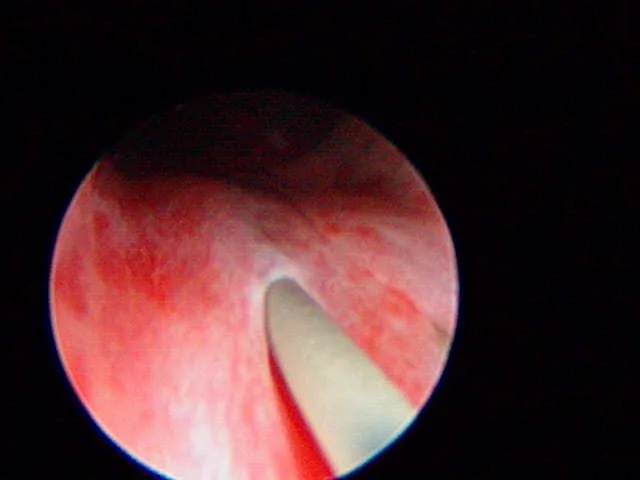

A

The plastic stent has been placed in the EU and the laser (green tip) is ablating the tissue over the stent.